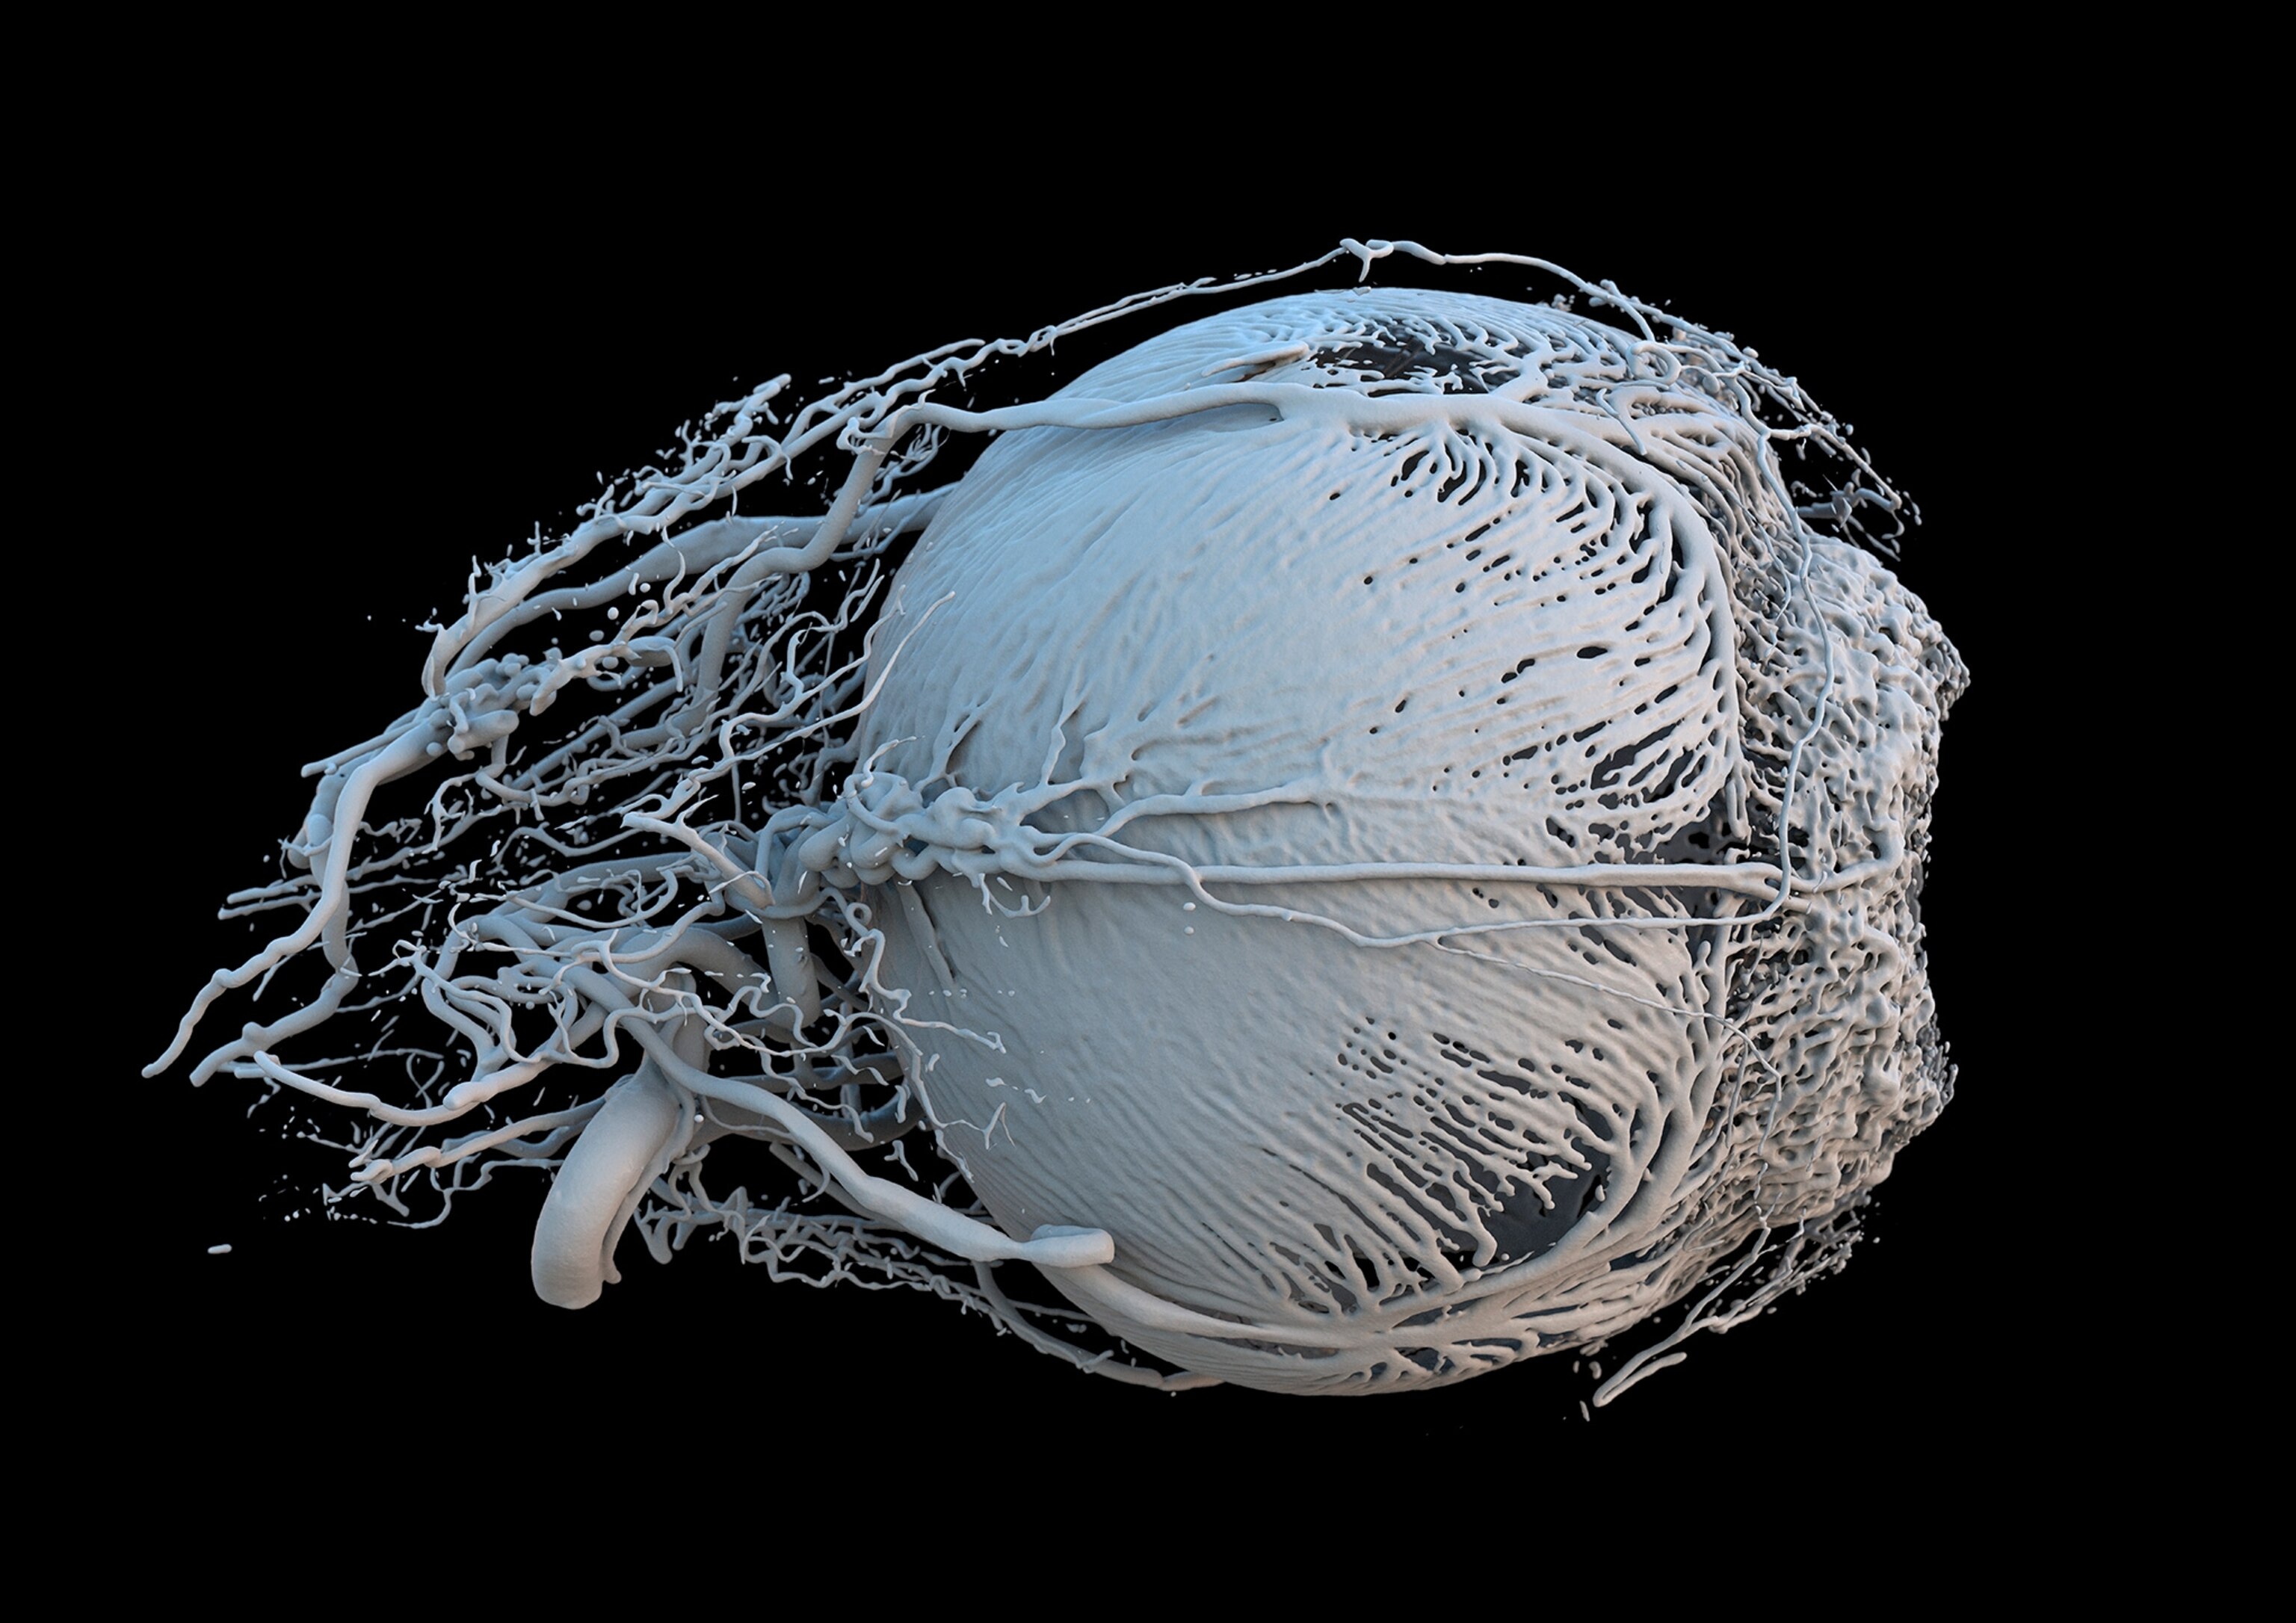

The contest also recognizes clinical photography with the Julie Dorrington Award. This year's recipient was Mark Bartley, for his extremely close view of an iris clip inserted on an eye to treat near sightedness and cataracts. The 70-year-old patient whose eye was photographed regained nearly all his vision following the surgery.